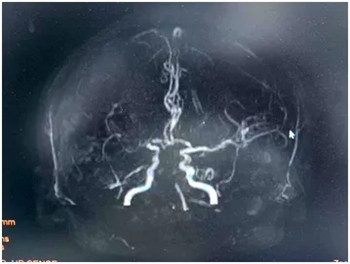

面对这突如其来的病情,绿色通道值班医生李金凤迅速响应,立即为患者安排了MRI(磁共振成像)和MRA(磁共振血管成像)检查以及头颅CT检查。MRI结果显示脑干梗死,而MRA则揭示了右侧大脑中动脉及基底动脉的闭塞。脑干作为生命中枢,其梗死可能导致严重的生命威胁,病情危急,刻不容缓。

▲ MRA显示:基底动脉及右侧椎动脉不显影,右侧大脑中动脉不显影